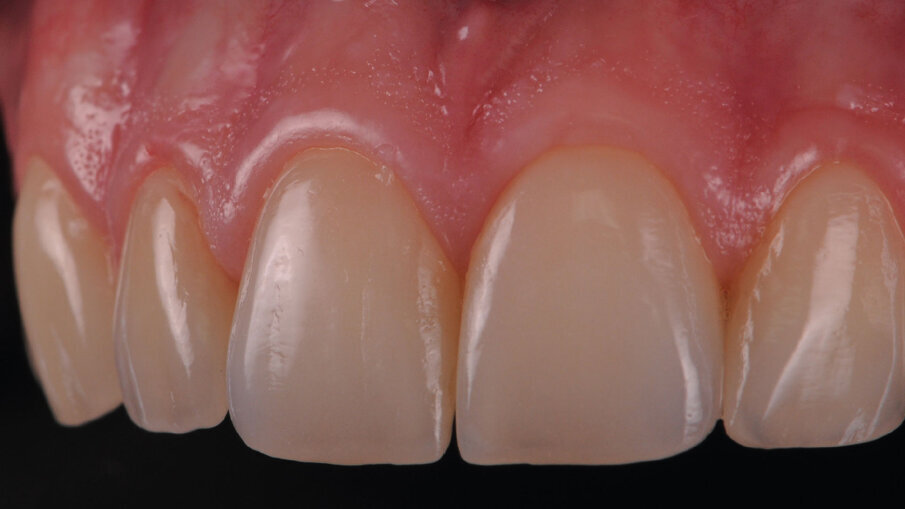

I gruppi posteriori inferiori sono stati finalizzati mantenendo la medesima dimensione verticale del mock up posteriore e quindi compensando il minus occlusale rispetto agli elementi 37 e 47 che come si era analizzato in precedenza erano morfologicamente e occlusalmente corretti (elementi dentali guida). Gli elementi 34-36 e 44-46 sono stati preparati per ricevere degli overlay in disilicato di litio. Si è optato per sei faccette in ceramica feldspatiche per il gruppo 13-23. Particolare attenzione e stata data alla scelta del colore inteso come croma e come valore per ottenere un effetto di “dente naturale”. La ceramica feldspatica infatti permette una lavorazione molto raffinata e curata nei minimi dettagli: le masse utilizzate vengono gestite e dosate con precisione ottenendo un effetto di transfluenza e profondità del colore. Quando si parla di faccette si tratta quindi una fascia molto delicata (in tutti i sensi) dell’Odontoiatria estetica, una combinazione di capacità clinico/tecniche per ottenere il miglior risultato possibile in pochi decimi di millimetro, ma oggi l’evoluzione dei materiali odontoiatrici e odontotecnici hanno ampliato il campo di applicazione, che ci consentono di ottenere risultati notevolmente biomimetici anche con trattamenti più conservativi da parte del clinico. Tendenzialmente le faccette sono indicate per casi dove le circostanze e le richieste sono altamente estetiche, pertanto ci permettono di modificare il colore, la forma e la dimensione, come nel caso clinico poco invasivo in questione. Tuttavia sfruttando al meglio gli spazi molto contenuti a disposizione del tecnico e i ragionati insieme in un lavoro d’equipe attraverso uno studio del caso con la ceratura diagnostica, che opportunamente provata in bocca attraverso l’utilizzo della mascherina siliconica, consente al clinico e soprattutto al paziente di verificare il design scelto per lui. Procedendo verso il lavoro definitivo, si sceglie la ceramica feldspatica per la sua efficacia biomeccanica e biomimetica. Dopo aver fabbricato il modello alveolare, queste faccette sono state cotte su monconi refrattari con i programmi di cottura dedicati, stratificando le masse indirizzate, tenendo presente il croma del substrato dentale naturale che contribuisce a determinare il colore finale. In uno spazio così contenuto, la differenza la fanno la selezione attenta del quantitativo di un effetto più o meno traslucente e la rifinitura della superficie curando al meglio le forme, i contorni e la tessitura superficiale con la delicatezza che una ricostruzione così sottile necessita (Figg. 10, 11).

Si è quindi proceduto “semplicemente” ad un “ripristino protesico” dei volumi dentali andati perduti. Estremamente interessante è anche l’analisi delle risposte tissutali dei margini gengivali specialmente degli incisivi, dove si apprezza con una “evidenza ottica” la ipertrofia positiva e controllata dei tessuti. Questo concetto mutuato dalle tecniche del sovracontorno tipico della preparazione verticale13 e non solo (tecnica della marginatura)14 dove si creano delle CEJ artificiali (in resina e poi ceramica), può essere applicata anche nel campo della restaurativa diretta e nelle fasi provvisorie utilizzando dei compositi lucidati a specchio (come è stato fatto nella pianificazione attenta dei margini del mock up utilizzato) al fine di indurre una maggiore stabilità marginale e una modifica del biotipo gengivale15, 16. È stata realizzata una pianificazione restaurativa parodontale pre-protesica occupando uno spazio libero invadendo in modo controllato (orizzontalmente) l’ampiezza biologica

Con questo case report gli autori vogliono trasmettere la loro visione e le loro personali indicazioni cliniche, che portano alla scelta di questo tipo di riabilitazione. Tali riabilitazioni devono essere sì estetiche mimetiche, ma soprattutto devono avere come “goal” il ripristino dei volumi dentali anatomicamente corretti sia nell’aspetto vestibolare che nell’aspetto incisale e occlusale. Il tutto pianificato con un’attenta analisi intra ed extra orale, prestando sempre attenzione alle richieste ed esigenze del paziente, che deve sempre essere al centro del progetto riabilitativo. Non secondaria l’attenzione dedicata alla “componente rosa” della riabilitazione, che deve essere gestita fin dalla fase provvisoria, al fine di avere una giusta “cornice” per i nostri manufatti che, sottolineiamo, sono pertinenza delle mani sapienti dei nostri odontotecnici (Figg. 12a, 12b).